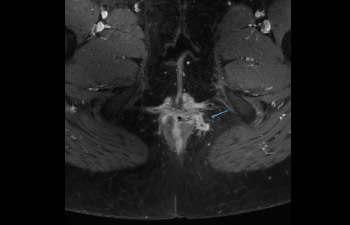

Pelvis

Pelvis con fístula